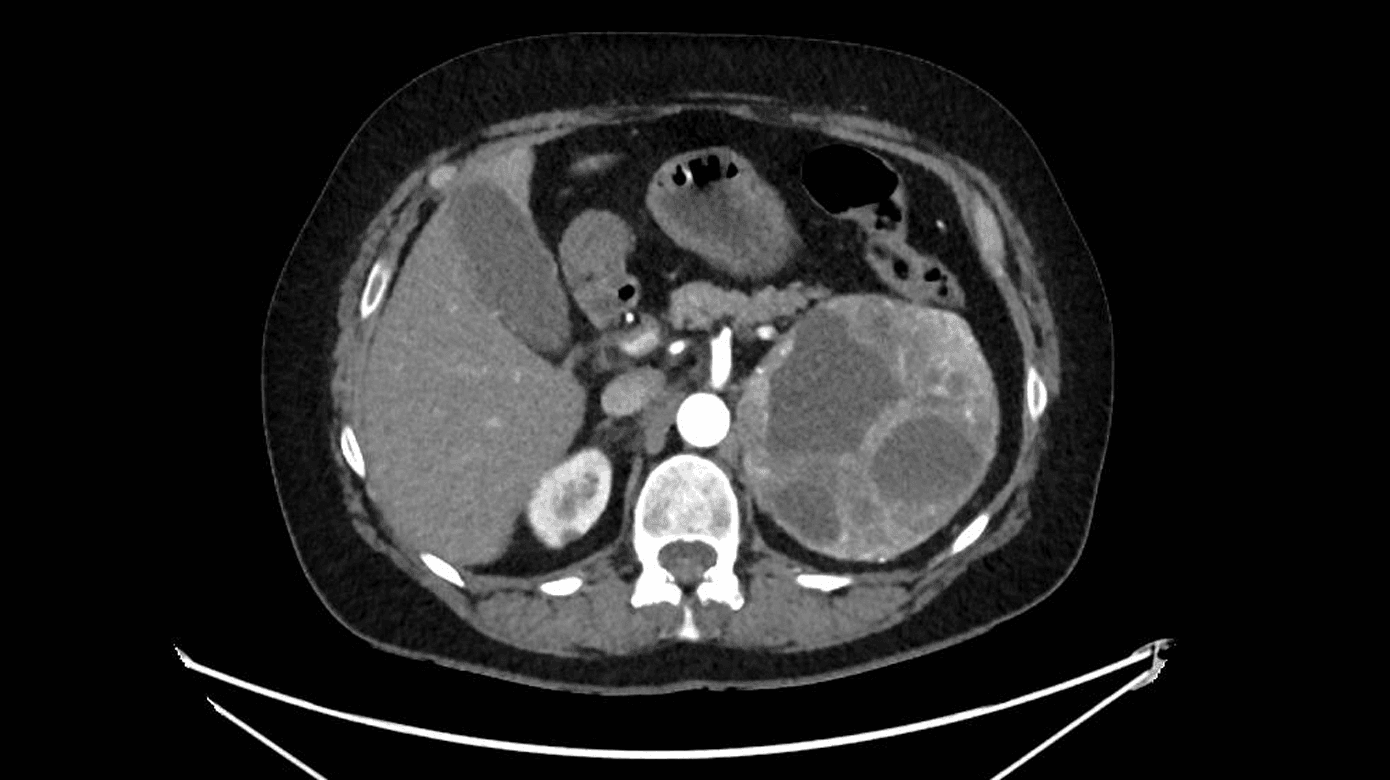

Patienten visiteredes til intensiv terapi, hvor hun udviklede tiltagende multiorganpåvirkning med sløret sensorium, respirationsinsufficiens, cirkulatorisk svigt og vigende diureser. Ekkokardiografi viste svært nedsat venstre ventrikel-uddrivningsfraktion (LVEF) 20% uden tegn til højresidig belastning. CT af thorax og abdomen var uden lungeemboli. Som bifund fandtes en 11 cm stor tumor over venstre nyre (Figur 1). Efterfølgende blodprøver viste massivt forhøjede værdier af 3-methoxyadrenalin 452,5 nmol/l (referenceniveau: < 0,47 nmol/l [2]) og 3-methoxynoradrenalin 203,5 nmol/l (referenceniveau: < 1,10 nmol/l). Der kræves ingen patientforberedelse forud for prøvetagning [2].